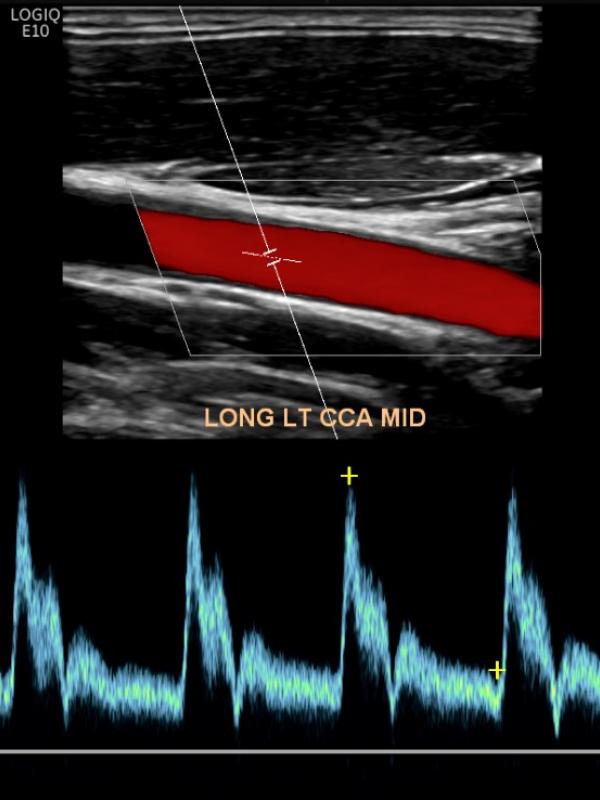

carotid ultrasound

Ultrasound imaging of the carotid arteries evaluates for plaque build-up or blockage. Referring providers order carotid ultrasound for a number of reasons. The most common reasons are: dizziness, stroke, blurred vision, or bruit discovered on physical exam.

Carotid ultrasound FAQ

• Is there any required preparation for a Carotid Ultrasound? No preparation is required.

• Who interprets the Carotid ultrasound exam? Sound Health Imaging contracts with Proscan Reading Services to read our exams. They are fellowship-trained, board-certified radiologists with subspecialty training.

• When and how will I get results? The Carotid ultrasound exam will be read by the radiologist within 24 hours of your study.  The results will be sent directly to your referring provider the week-day after your exam.

• How do I schedule my Carotid ultrasound at Sound Health Imaging? A provider’s order is required for the Carotid ultrasound. When you see your healthcare provider, let them know you would like to have your ultrasound scheduled at Sound Health Imaging. Or, after you see your provider, you can call our office and make your ultrasound appointment and then bring your order with you at the time of exam.